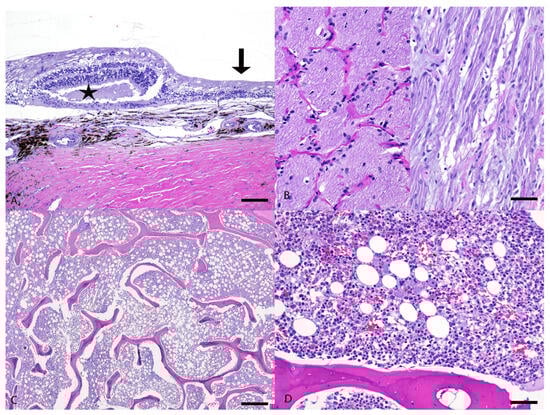

3.2. Pathological Examination